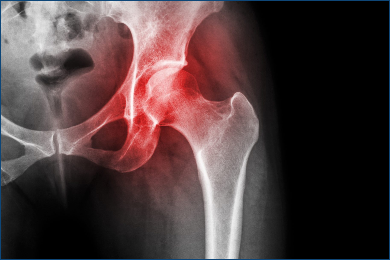

The hip joint is one of the largest and most important joints in the body. It connects the thigh bone to the pelvis and allows for a wide range of motion. However, hip problems and diseases can cause pain, stiffness, and limited mobility, affecting daily life and overall well-being.